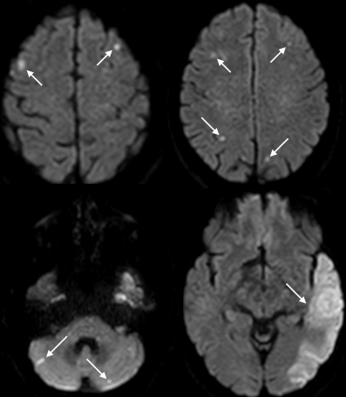

Paciente C.A.L., 61 anos, sexo masculino, portador de hiperplasia prostática benigna, foi admitido no Hospital Geral de Palmas com relato de confusão mental súbita, sendo evidenciada na admissão hospitalar afasia global. O exame de imagem da chegada evidenciava áreas de isquemia em território de artéria cerebral média e posterior esquerdas, bem como múltiplos focos de restrição à difusão em hemisférios cerebelares, subcortical frontal, parietal bilateral, sugerindo etiologia embólica (sinal dos 3 territórios), conforme Figura 1.

Figura 1: Sinal dos 3 territórios. Imagens de ressonância nuclear magnética de crânio ponderada em difusão (RNM – DWI) mostrando múltiplas lesões de alta intensidade de sinal nos hemisférios cerebrais e cerebelares envolvendo três territórios vasculares diferentes.

O exame de imagem realizado na admissão do paciente mostrava isquemia aguda na RNM ponderada em difusão, bilateral em circulação anterior e posterior, sendo esse achado denominado sinal dos três territórios, considerado um marcador radiográfico de acidente vascular cerebral associado à malignidade. O sinal dos três territórios tem grande especificidade para hipercoagulabilidade decorrente de neoplasia (96,4%), mas baixa sensibilidade (23,4%) (NOUH et al., 2019; YILDIRIM et al., 2023).